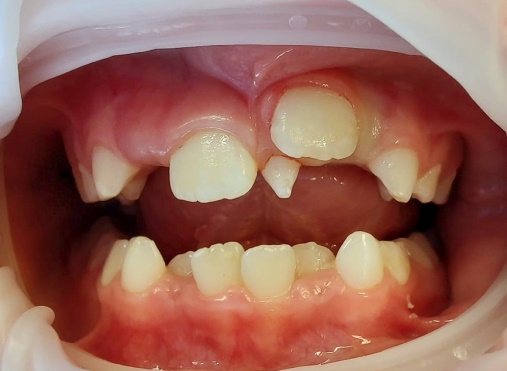

R21 chưa mọc, R11 đã mọc (a), Răng thừa (b), R22 (c) (b)Răng thừa thứ nhất, (a) răng thừa thứ 2, (c) R21 ngầm chưa mọc Phẫu thuật lật vạt:(a) răng thừa thứ 1, (b) R21 ngầm, (c) R22

Răng thừa thứ 1đã được nhổ Bộc lộ răng thừa thứ 2 Hình ảnh 2 răng thừa

Hình ảnh sau phẫu thuật 6 tháng, R21 đã mọc lên sau khi loại bỏ 2 răng thừa

Hình 4: Minh họa cho phẫu thuật lấy răng thừa đơn thuần ở một bé trai 9 tuổi